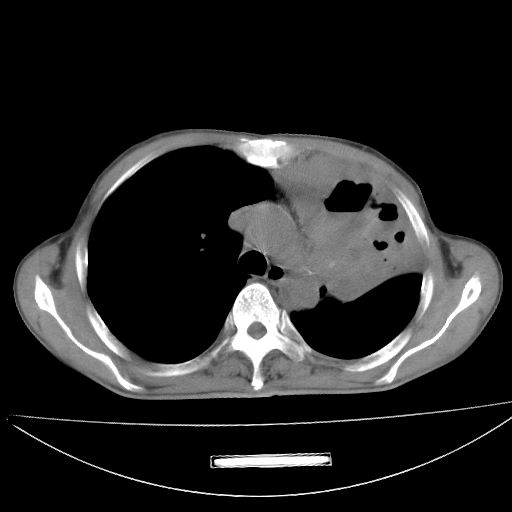

以下是引用杀毒软件在2009-4-28 17:58:00的发言:[br]考虑----左肺慢性肺脓肿形成继发上叶含气不良---抗炎后复查---待排肿瘤所致[br][br][本贴已被 杀毒软件 于 2009-4-28 18:01:26 修改过]